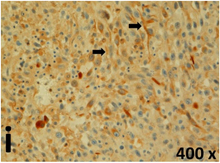

Table 2 presents the haematoxylin and eosin (H & E) staining and immunohistochemical (glial fibrillary acidic protein [GFAP] and Ki-67) results of the three groups. H & E staining revealed that the central necrotic and tumour areas rapidly and markedly increased in the control group (a and b). The central necrotic area expanded more slowly in the BIC group, and some calcification was observed (c and d). The central necrotic and tumour infiltration areas decreased in the BICC group (e and f). Moreover, GFAP expression markedly decreased in the control group (g and h). The GFAP expression was suppressed in the BIC (c and d) and BICC (e and f) groups; the suppression was higher in the BIC group. In both the BIC and BICC groups, the GFAP expression progressively increased. The Ki-67 labelling index was 22.84% ± 7.93% and 45.98% ± 11.57% in Weeks 4–6 and 8–12, the Ki-67 index was high and markedly increased in the control group. By contrast, this index was 15.98% ± 7.31% in Weeks 4–6 and decreased to 11.41% ± 4.13% in Weeks 8–12 in the BIC group. This index was much lower in the BICC group than that in the control and BIC groups (7.29% ± 1.35% and 0.79% ± 0.55% in Weeks 4–8 and 10–14, respectively).

H & E staining revealed central necrosis (black arrows; a–f), GFAP expression (g–l), and Ki-67-positive nuclei (m–r). The black triangles indicate the blood vessels in brain tissues (a–f). The central necrosis area increased rapidly in the control group (a and b) and increased more slowly in the BIC group (c and d), and decreased in the BICC group (e and f). Almost no GFAP expression was observed in the control group (g and h), slight GFAP expression was observed at 4–6 weeks (i), and increased GFAP expression was observed at 8–12 weeks in the BIC group (j). More obvious GFAP expression was observed in the BICC group (k and l). The Ki-67 indices were 22.84%, 45.98%, 15.98%, 11.41%, 7.29%, and 0.79%, as shown in pictures m, n, o, p, q, and r, respectively.

The proliferative index is a potent biological marker for quantitatively estimating the growth of neoplasms, thus aiding in the identification of the prognosis of patients with neoplasms. The Ki-67 labelling index is one of the most effective methods for estimating the proliferative index of the CNS [40, 41]. A case-specific growth period of a GBM was recently suggested; the period was shorter and longer in tumours with high and low cell proliferation indices, respectively [42]. GBM and anaplastic astrocytoma occur from astroglial cells, and GFAP is the most widely used marker of astroglial cells. Malignant astrocytic tumours are GFAP negative, and numerous high-grade gliomas appear to have lower GFAP expression [43, 44]. Similarly, a steady transfection of rat astrocytoma C6 cells with GFAP cDNA suppressed the cells proliferation and extended the cellular processes [45]. In our study, H & E staining revealed that the central necrotic and tumour areas gradually increased and decreased in the BIC and BICC groups, respectively, after the implantation of nanofibrous membranes. The GFAP expression and Ki-67 labelling index demonstrated the most severe malignancy in the control group, followed by the BIC group, and the least severe malignancy in the BICC group.